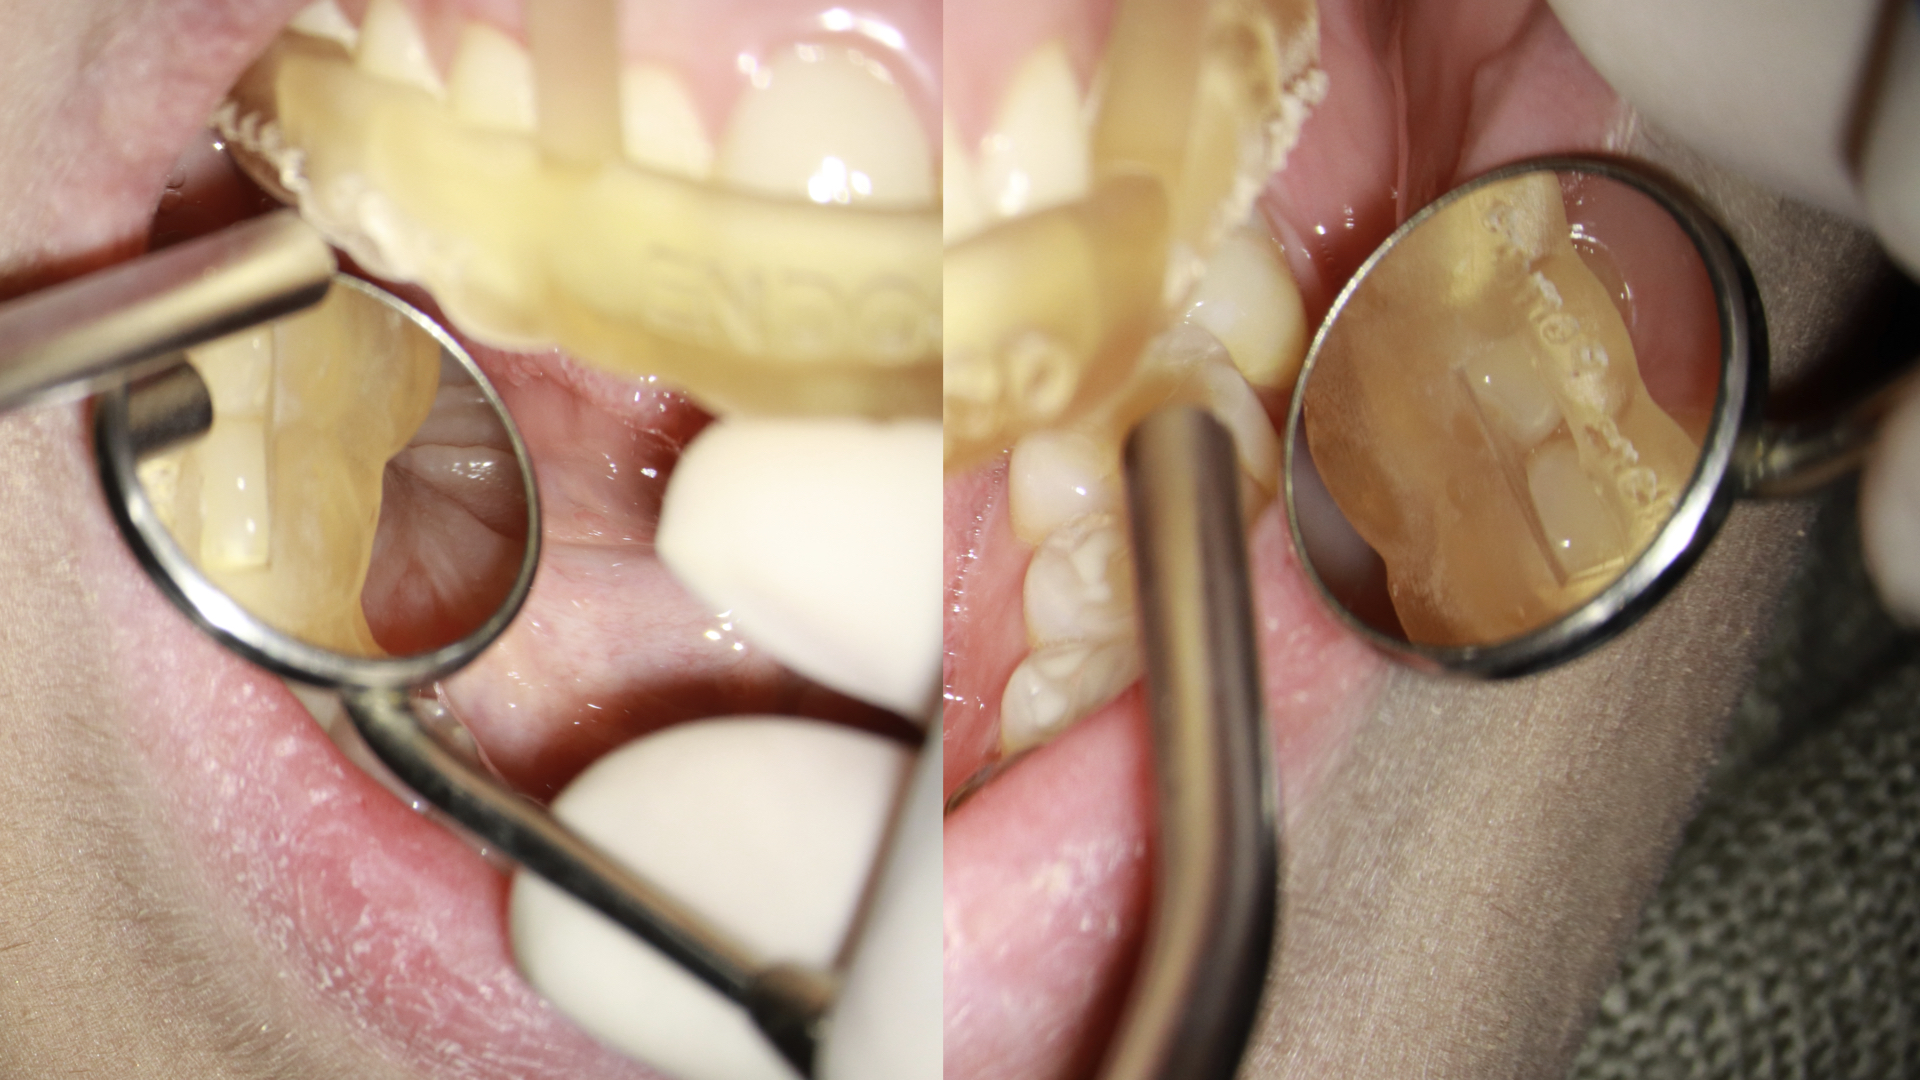

- Prova do endoguide em boca, avaliando a adaptação distal sobre a oclusal dos dentes e também nas janelas que encontramos no guia (figura 4).